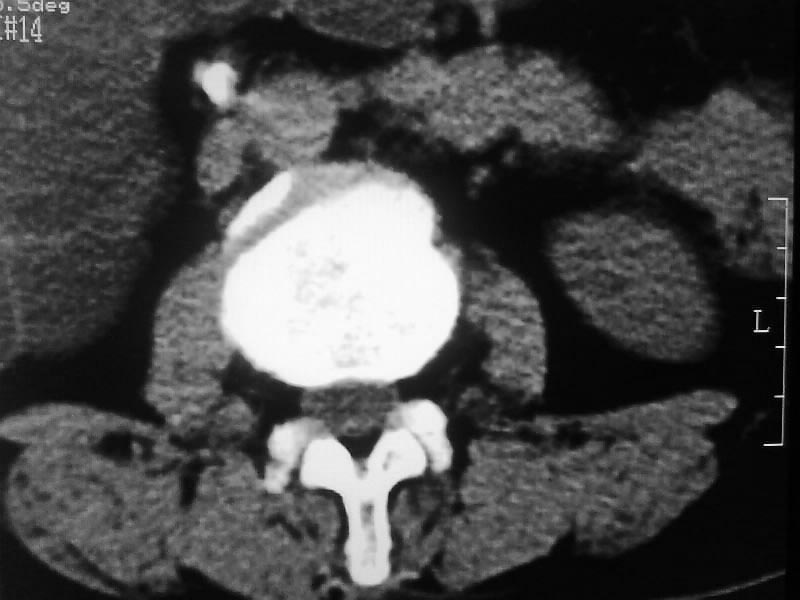

定位相示l2呈楔形改变(ct示陈旧性骨折改变,图像未传),l4.5椎体融合,以下是l4.5ct平扫.请各位看看,

考虑结核(有破坏、硬化及死骨)。

1、三四椎体结核,2、水平骶椎。

1、l1压缩性骨折(陈旧性)。

2、l3、4椎体结核。

就是腰1压缩性骨折,腰3\\4椎体结核(融合),水平骶椎.

支持 l1椎体陈旧性压缩性骨折;l3、4椎体结核(融合);水平骶椎。